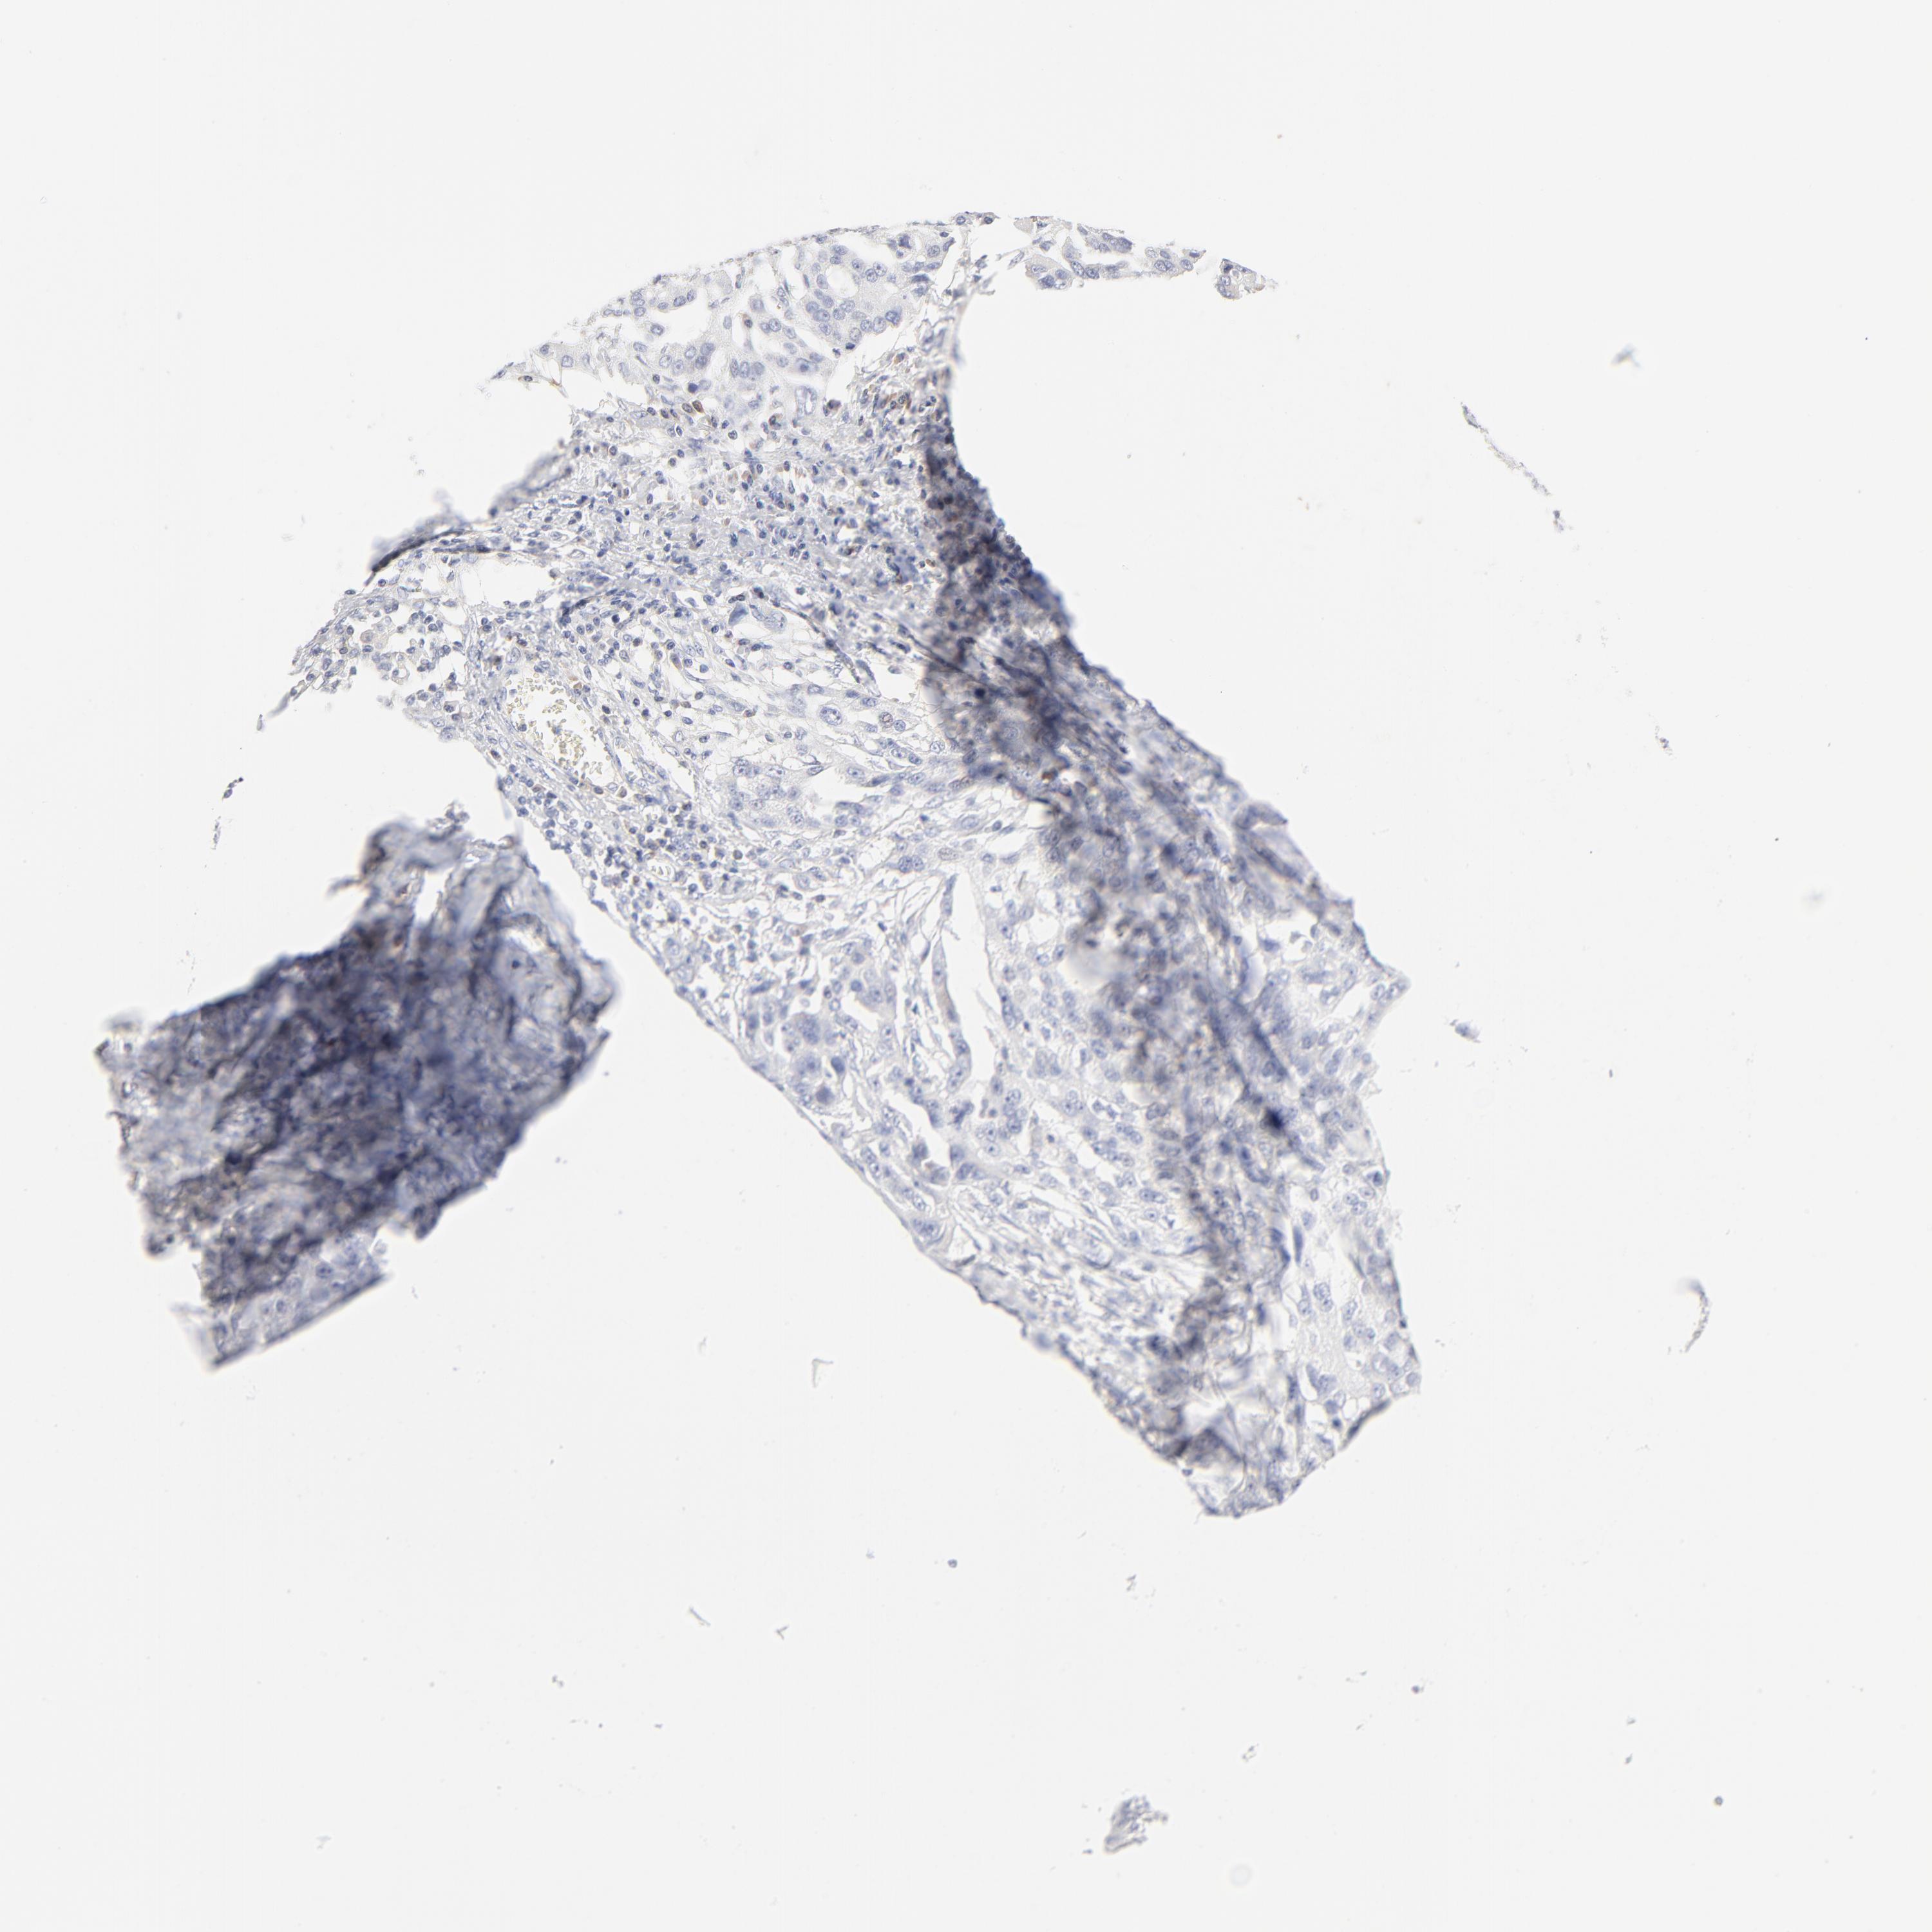

OVARIAN CANCER - Protein expressioni

A mouse-over function shows sample information and annotation data. Click on an image to view it in a full screen mode. Samples can be filtered based on level of antibody staining by selecting one or several of the following categories: high, medium, low and not detected. The assay and annotation is described here.

Note that samples used for immunohistochemistry by the Human Protein Atlas do not correspond to samples in the TCGA dataset.

Antibody stainingi

Antibody staining in the annotated cell types in the current human tissue is reported as not detected, low, medium, or high, based on conventional immunohistochemistry profiling in selected tissues. This score is based on the combination of the staining intensity and fraction of stained cells.

Each image is clickable and will lead to virtual microscopy that enables deeper exploration of all samples and also displays staining intensity scores, fraction scores and subcellular localization as well as patient and tissue information for each sample.

Antibody HPA003371

Staining

High

Medium

Low

Not detected

Intensity

Strong

Moderate

Weak

Negative

Quantity

>75%

75%-25%

<25%

None

Location

Nuclear

Cytoplasmic/membranous

Cytoplasmic/membranous,nuclear

Cystadenocarcinoma, mucinous, NOS

Carcinoma, endometroid

Cystadenocarcinoma, serous, NOS